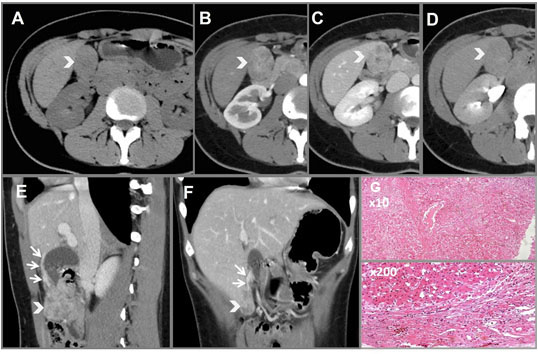

A previously well 9-year-old boy presented with intermittent left upper quadrant pain, anorexia, and weight loss over six months. His past medical history was significant for being born preterm at 34 weeks’ gestation and requiring ventilatory support as a neonate. Computed tomography (CT) scan (Figure 1 and Figure 2) showed a 10 cm encapsulated spherical mass appearing to arise from the pancreatic tail. The working diagnosis was a cystic pancreatic tumour, and he was referred for further management.

Figure 2: CT axial view showing the cyst and its relations to the left kidney and vasculature.